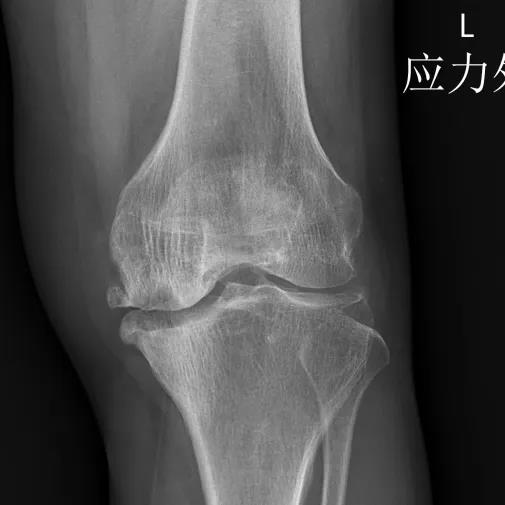

▲术前

▲术后